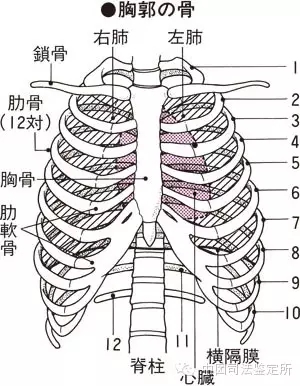

肋骨骨折 医学百科网

多根肋骨骨折 多根肋骨骨折的治療 多根肋骨骨折的原因 多根肋骨骨折怎麼辦 症状百科